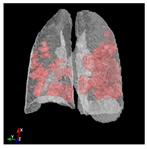

3.6. Post-Processing: 3D Projection

To generate a 3D projection from the 2D output, a post-processing step is required. This step involves aggregating the CT image slices and transforming them into a coherent 3D representation. In this process, the Mayavi [] library in Python serves as a valuable tool for facilitating the conversion of the 2D model output into a 3D representation.

The process begins by obtaining segmentation masks for each individual slice of the CT-scan. These masks provide information about the different regions within the lung. Next, the segmented slices are merged to create a unified representation. This merging process involves swapping the axes of the segmented data, ensuring that the resulting 3D projection can be visualized as a cohesive volume.

The utilization of the Mayavi library streamlines the transition of the 2D model output to a 3D representation. This library offers robust functionality for transforming and displaying the segmented data in a three-dimensional space. By employing Mayavi, the proposed approach enhances diagnostic capabilities, providing clinicians with a comprehensive 3D visualization of lung structures and infection areas.

In Table 6, a comparison of the ground truth and prediction results of each model is presented in 2D, along with the 3D projection of each model. The visual analysis of the predictions provides additional insights into the performance of each model. The visualizations demonstrate that Attention UNet captures the intricate details of the lung construction more accurately, resulting in more precise segmentation of the infected areas compared to other models.

Table 6.

Comparison of ground truth and model prediction results using UNet, LinkNet, Attention UNet, UNet 3+, and TransUNet.